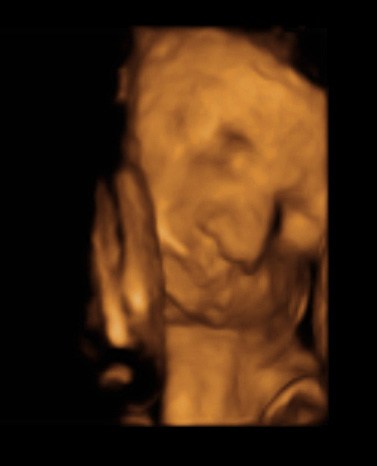

Det er da en rigtig god julegave. Jeg kan forestille mig, hvor spændt man er på, hvordan prinsessen ser ud. Så er det et rigtig godt "redskab".

Faren må være pavestolt, når det er så tydeligt, at hun ligner ham